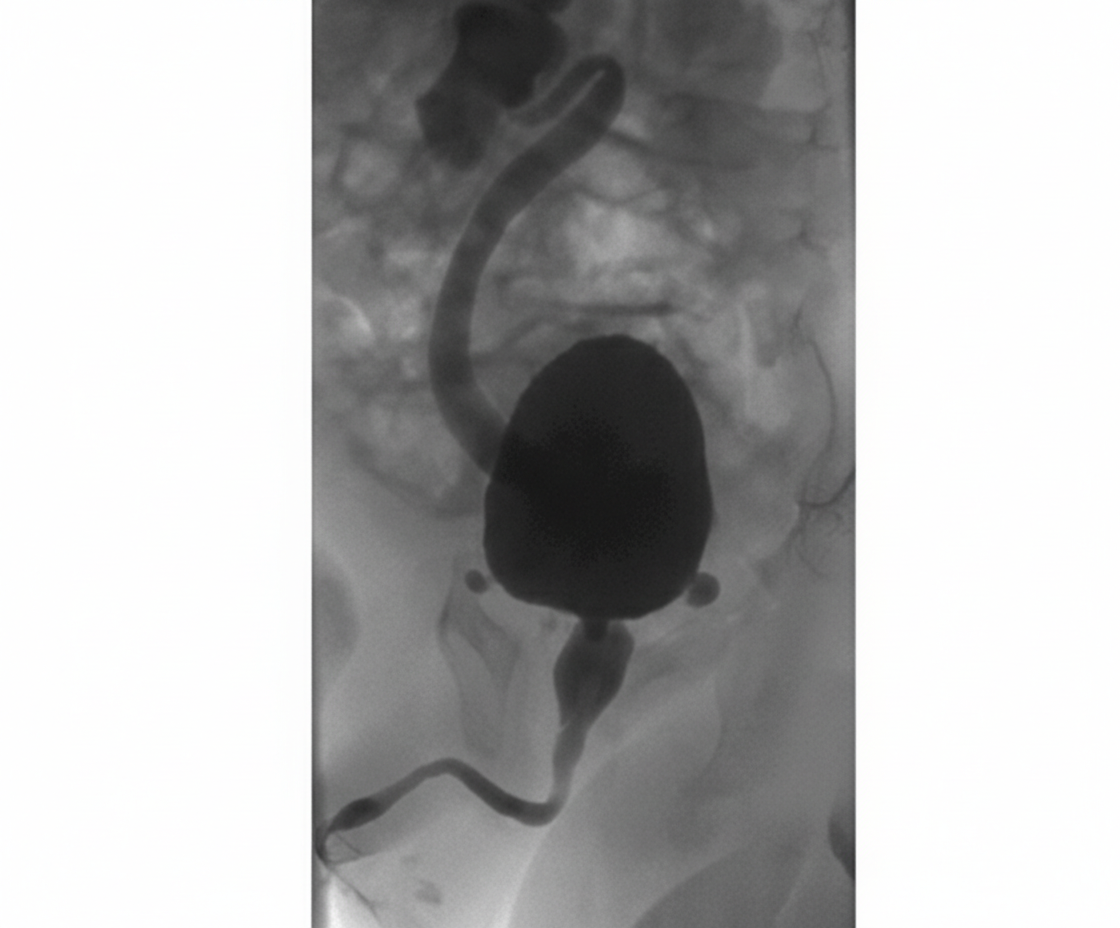

A 3-year-old child presents to the OPD with a history of recurrent urinary tract infections, poor urinary stream, and difficulty voiding. The radiological image is shown below. What is the most appropriate management?

A 2-year-old boy presents with a history of recurrent urinary tract infections, poor urinary stream, and failure to thrive. A voiding cystourethrogram (VCUG) is performed, and the images provided show dilated posterior urethra and a thickened bladder wall with a keyhole appearance. Based on these findings, the diagnosis of posterior urethral valves (PUV) is made. What is the management for this condition?

Explanation: ***Endoscopic ablation*** - The image shows a distended bladder with a dilated, elongated posterior urethra and a narrow stream of contrast beyond the bladder neck, characteristic findings of **posterior urethral valves (PUV)**. - **Endoscopic ablation (incision or fulguration)** of the valves is the definitive treatment for PUV to relieve obstruction and prevent further kidney damage. - This is the **gold standard primary treatment** for PUV in children who are large enough to undergo the procedure safely. *Dilation of urethra* - **Dilation** is generally ineffective because PUV are folds of tissue that require incision rather than simple stretching. - This approach does not address the underlying anatomical obstruction caused by the valves and could potentially cause damage to the urethra. *Dilation of urethra and bladder* - **Dilation of the urethra** is not an effective treatment for PUV. The bladder is already dilated due to the obstruction, and further dilation would not resolve the issue. - This approach would not remove the obstruction and could worsen bladder function or lead to further complications like reflux. *Conservative* - **Conservative management** with watchful waiting is not appropriate for PUV, as untreated obstruction can lead to progressive and irreversible kidney damage, bladder dysfunction, and recurrent UTIs. - Timely intervention is crucial to preserve renal function and improve long-term outcomes in boys with PUV. *Vesicostomy* - **Vesicostomy** (temporary bladder diversion) is reserved for specific scenarios such as neonates or very young infants too small for safe endoscopic ablation, severe hydronephrosis with renal failure, or failed primary ablation. - In this **3-year-old child**, endoscopic ablation is preferred as the primary definitive treatment rather than temporary diversion, which would require a second procedure later.

Explanation: ***Endoscopic valve ablation*** - This is the **definitive treatment** for posterior urethral valves (PUV) as it directly addresses the anatomical obstruction. - Ablating the valves with a **cystoscope** relieves the outflow obstruction, preventing further damage to the bladder and kidneys. *Antibiotic prophylaxis and monitoring* - While important for managing recurrent UTIs and preventing future infections in children with PUV, it does **not address the underlying anatomical obstruction**. - Without surgical intervention, the obstruction would persist, leading to progressive urinary tract damage despite antibiotic use. *Suprapubic cystostomy* - This procedure involves placing a catheter directly into the bladder via the abdominal wall to **divert urine**. - It is typically a **temporary measure** used for initial decompression in severely ill patients or those with complete obstruction, not the definitive management. *Urinary diversion with vesicostomy* - Vesicostomy creates an opening between the bladder and abdominal wall for temporary urinary diversion. - This may be used in **very young infants** or critically ill patients as a temporizing measure, but **endoscopic ablation remains the definitive treatment**. *Observation with follow-up imaging* - **Observation is not appropriate** for symptomatic PUV due to the risk of progressive and irreversible renal damage. - The condition requires **prompt intervention** to relieve the obstruction and prevent long-term complications like renal failure.